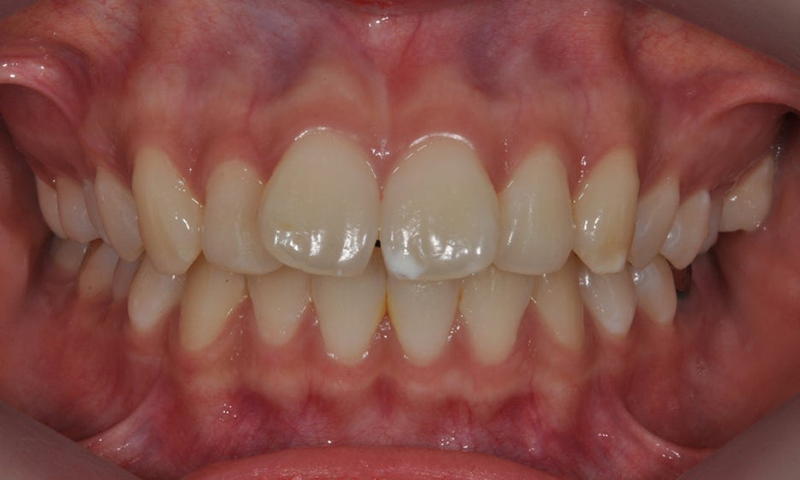

front teeth white spots

white spots after orthodontics

Before & After photos of ICON Treatment